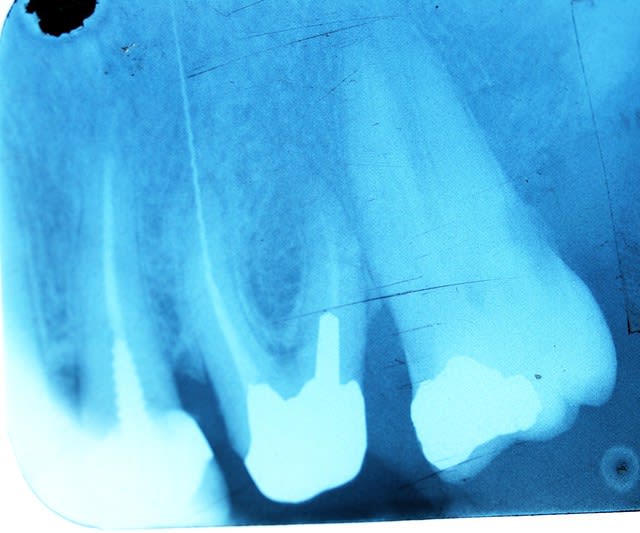

Et c'est reparti ce matin de plus belle : pulpite. L'embarras du choix -))))

C'est pas comme si on faisait des radios de controle régulièrement hein ? -))))

Capture d e cran 2015 11 30 09.34 - Eugenol